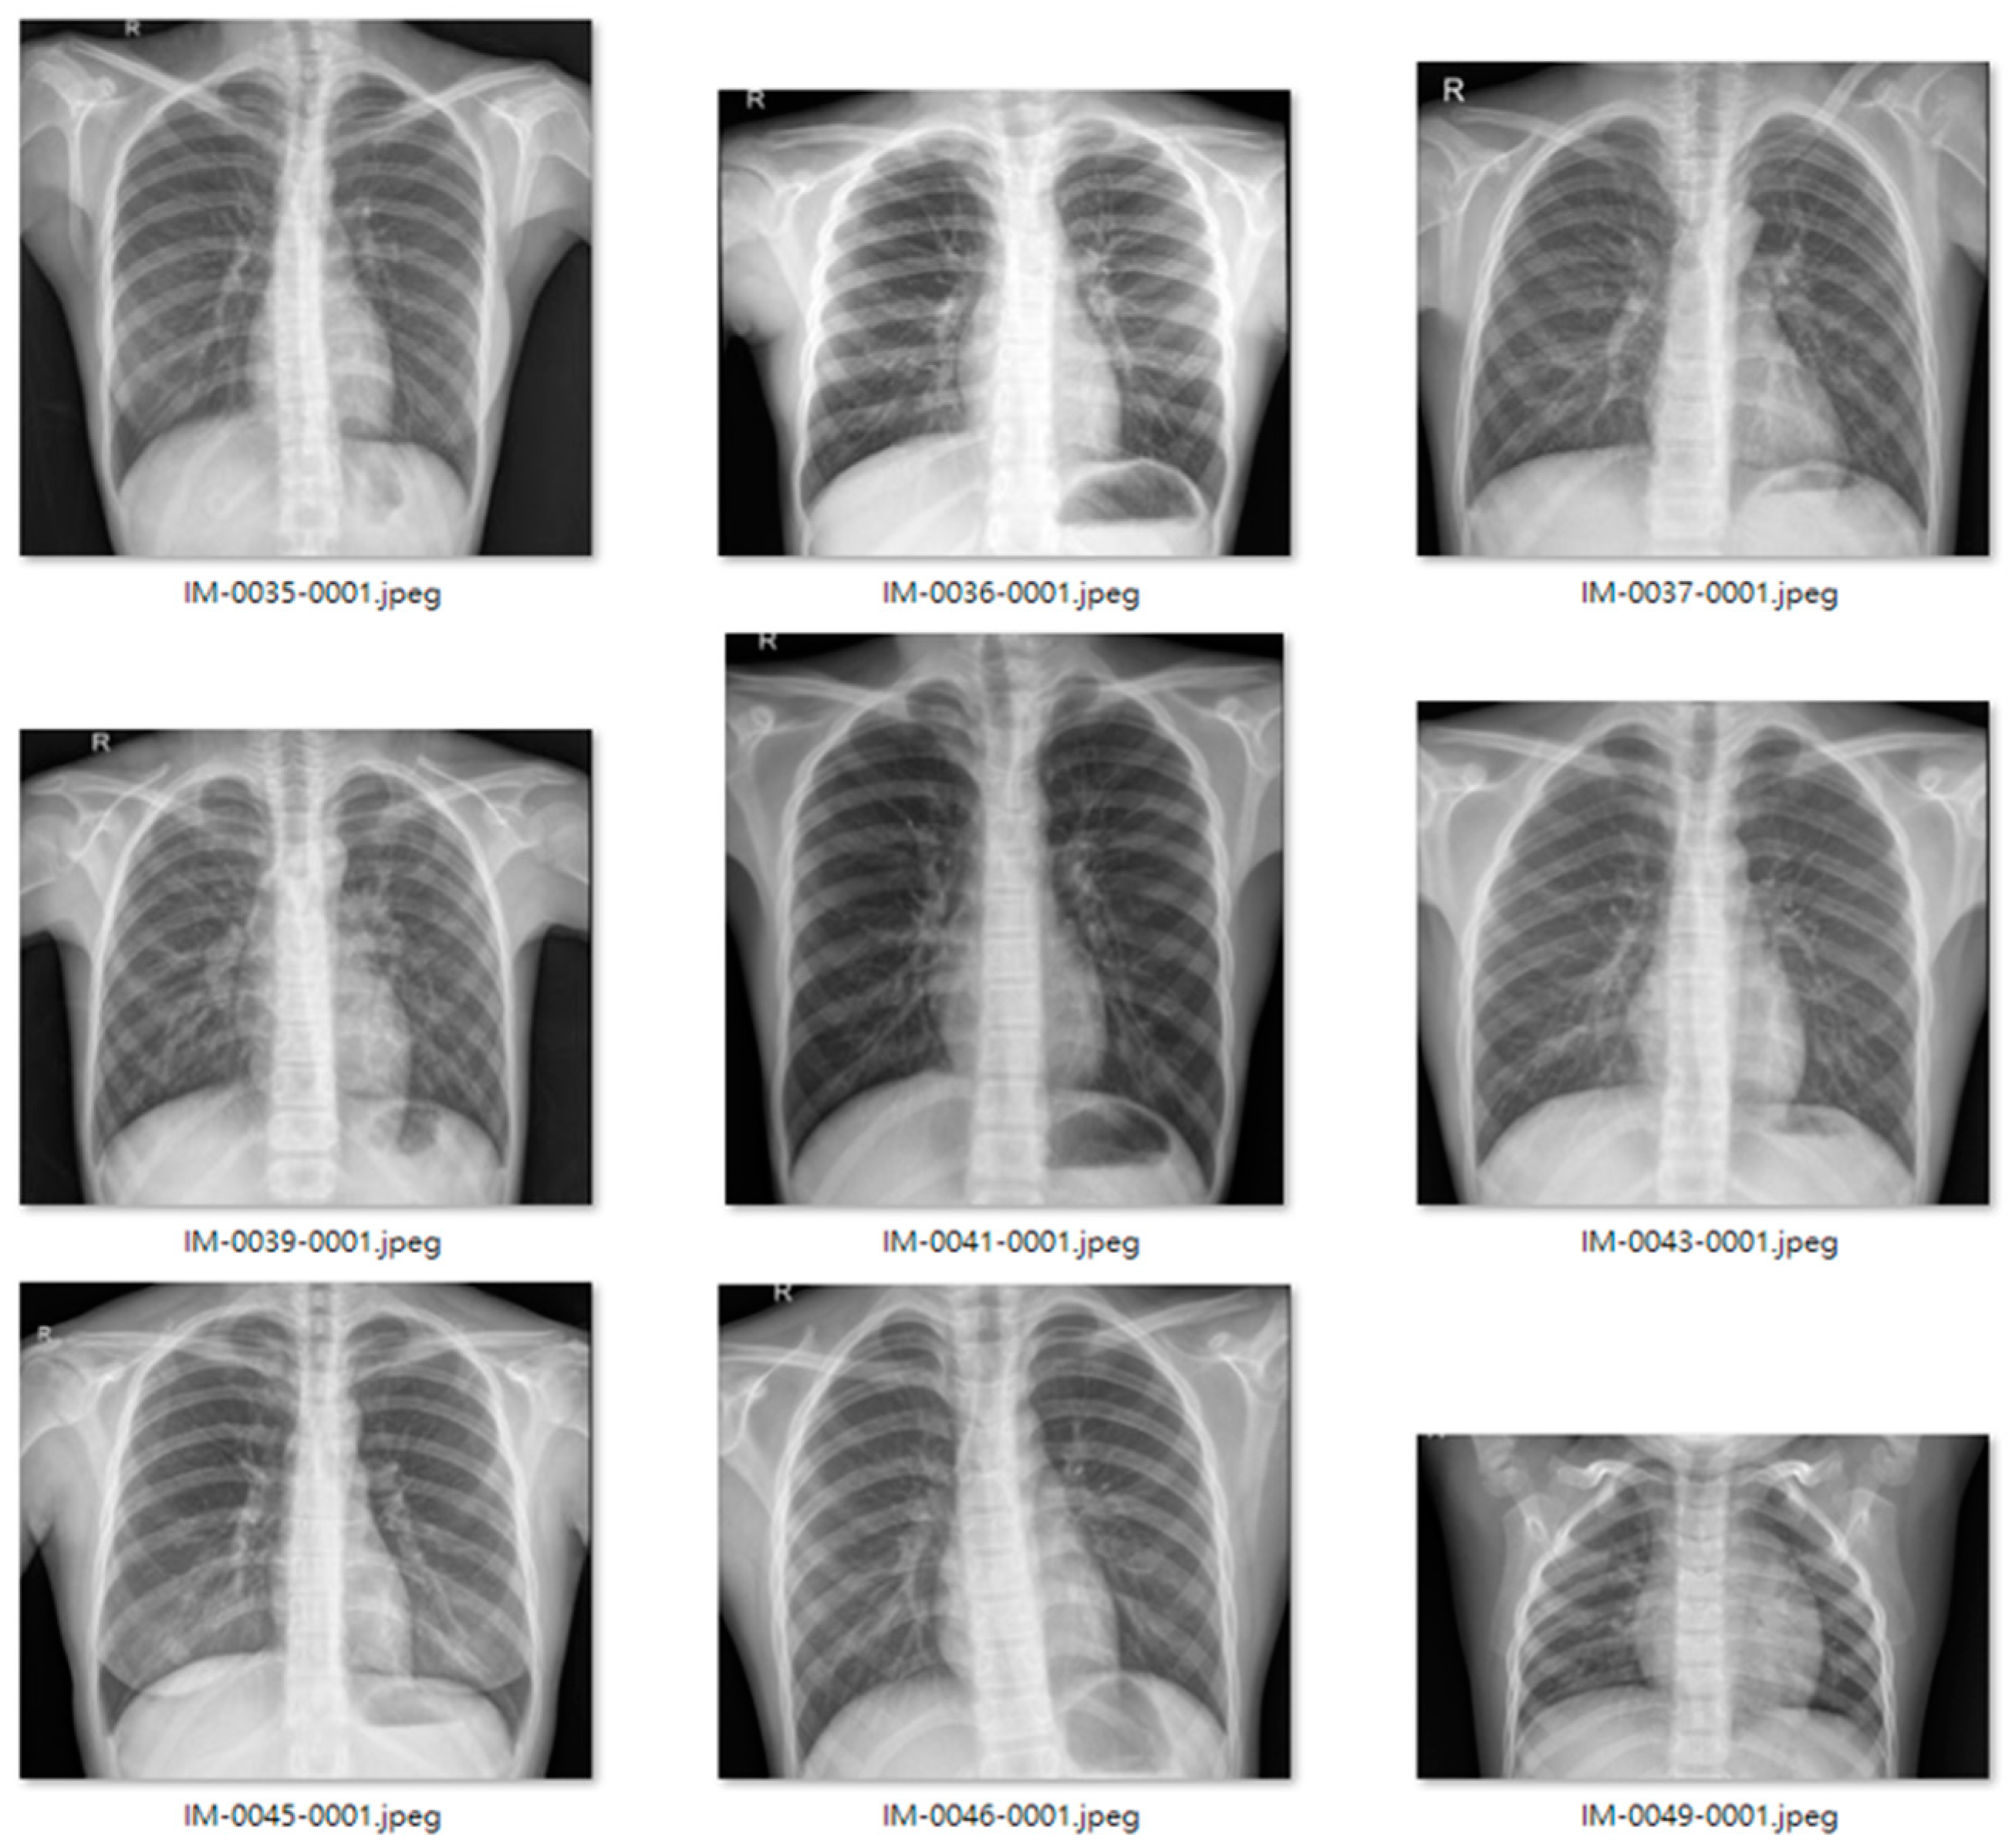

We used an open-source dataset provided by the Kaggle data science competition platform for training (https://www.kaggle.com/paultimothymooney/chest-xray-pneumonia accessed on 25 March 2018) [31]. The dataset comprised thoracic cavity images from child patients (1 to 5 years old) from the Guangzhou Women and Children’s Medical Center, China. These images were classified by two expert physicians and separated into training, test and validation sets. Figure 8 displays the dataset structure, with training sets including 1341 and 3875, test sets 234 and 390, validation set 8, and eight normal and pneumonia images, respectively. Figure 9 and Figure 10 show examples of normal and pneumonia thoracic cavity X-ray images, respectively.

Figure 10. Example pneumonia thoracic cavity X-ray images from the study dataset [31].